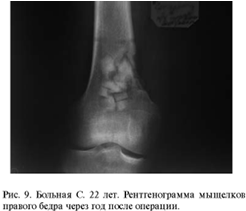

Для сравнения приведены примеры замещения

опухолей мыщелков бедренной кости хроносом и пористым углеродом.

Сравнение замещения дефектов губчатой кости

хроносом и пористым углеродом показало, что после имплантации хроноса через год

рентгенологически определяются фрагменты имплантированного материала, т. е. его

перестройка к этому времени не заканчивается. При использовании пористого

углерода определить материал на рентгенограммах крайне сложно. Положительным

качеством пористого углерода является возможность врастания в него сосудов и

костной ткани, следовательно, - восстановления питания субхондраль-ной зоны

кости и самого хряща.

Таким образом, пористый ячеистый углерод может

быть использован для замещения крупных дефектов губчатой костной ткани